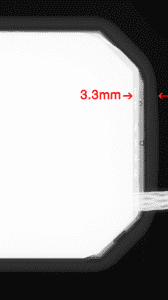

For historical reasons, most sensors place necessary electronics near the edge where the cord exits the sensor. The result is a dead space of up to 6mm, since the electronics cannot also be part of a sensor’s active imaging area. So, for bitewing purposes, the very edge used to capture the canine/premolar contact may not capture any image at all for its first 3-6mm. Clinicians who regularly place sensors instantly see this as a problem.

Figures 2a through 2d demonstrate how XDR’s imaging area extends further toward the sensor’s mesial edge. XDR has patented this approach under US #9357972B .